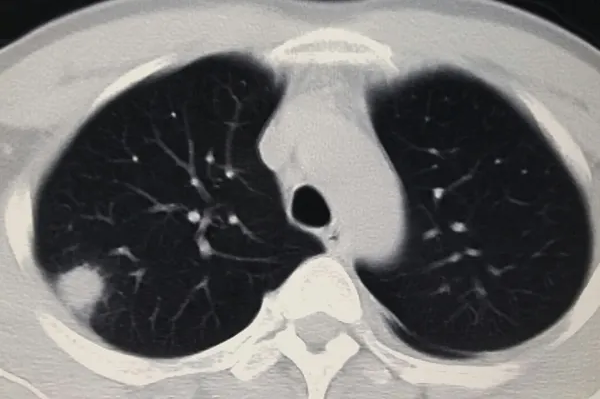

肺部有结节是怎么回事?要紧吗?

细菌、病毒感染、环境人体免疫机制导致肺结节,这取决于具体原因。长期在多尘环境中,肺部被吸入的粉尘包裹,形成颗粒和局部结节。金黄色葡萄球菌感染结核分枝杆菌可引起肺炎。炎症消退后,一些肺部留下纤维化钙化病变,形成结节。这个结节通常是良性的,不是很严重。如果结节生长过快,则可能是更严重的恶性转化,通常与恶性肿瘤有关。